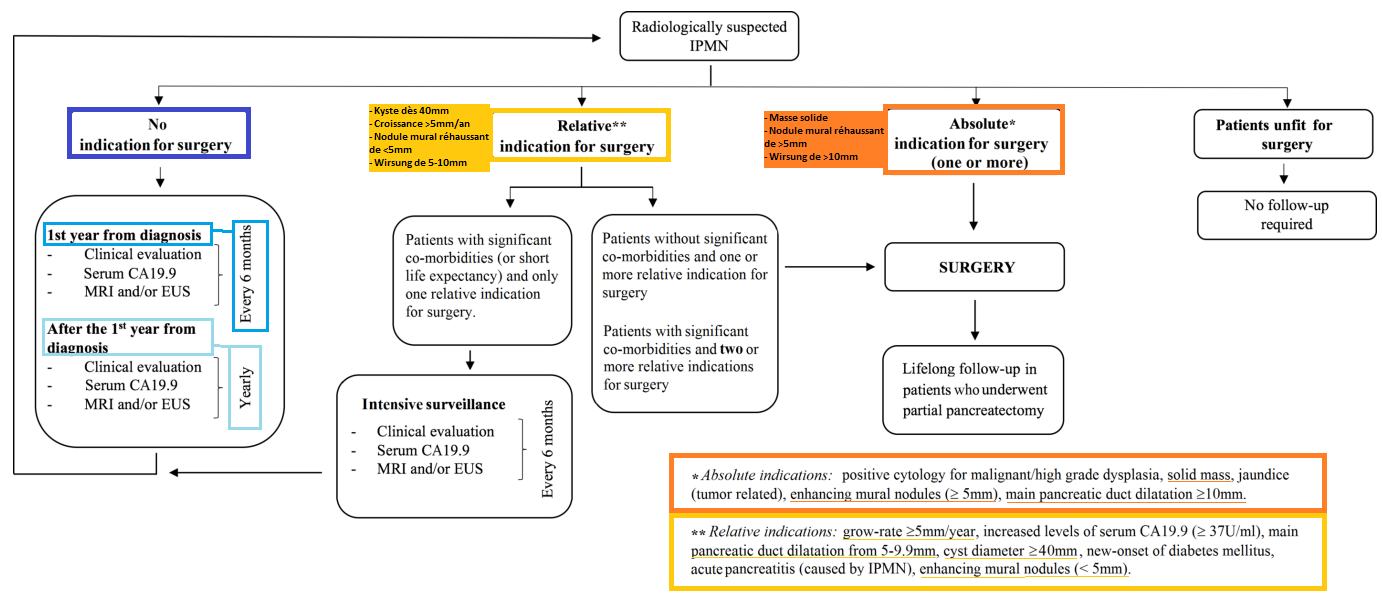

Guideline Européennes